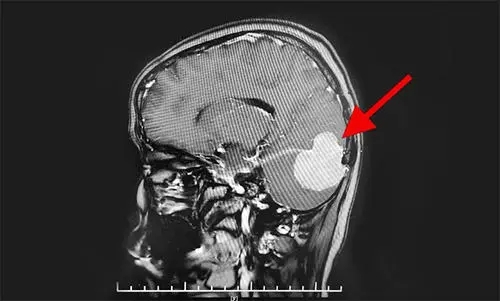

小腦幕腦膜瘤(tentorialmeningionma)起源于小腦幕的任何一部分,可單純生長于幕上或幕下,也可幕上、幕下同時發(fā)生。臨床少見,小腦幕腦膜瘤占顱內腦膜瘤的3%~5%。發(fā)病年齡40一50歲,女性明顯多于男性。臨床分型較多。分為幕上型、幕下型和啞鈴型。由于小腦幕在顱內占據(jù)的范圍大,因此,小腦幕腦膜瘤的分類存在困難,Samii教授等人將小腦幕腦膜瘤分為六類:鞍旁(海綿竇)區(qū)腦膜瘤、小腦幕腦膜瘤、鐮幕腦膜瘤、巖斜區(qū)腦膜瘤、腦橋小腦角腦膜瘤和竇匯旁腦膜瘤。其中,單純的小腦幕腦膜瘤少見。

1.依靠CT掃描或MRI檢查。血管造影對檢查橫竇通暢情況有幫助。在影像診斷上應該注意了解:①腫瘤向幕下還是幕上生長。②腫瘤與橫竇的關系。③小腦幕切跡前的腫瘤與腦干的關系。